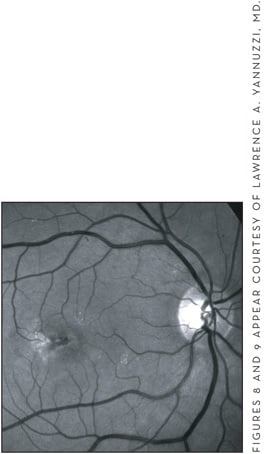

Most patients with IPT have bilateral disease on presentation, although many will only complain of visual changes in 1 eye. Common symptoms include blurred vision, metamorphopsia, positive scotoma due to exudation from ectatis, and incompetent retinal capillaries.34 VA is usually normal in the nonproliferative stage of the disease and only becomes affected when vessel dilation and blunting begins to be seen on biomicroscopy. In the proliferative stage, subfoveal atrophy and subretinal neovascularization late in the disease cause significant loss of central VA.34 Early in the disease the clinical exam is significant for loss of retinal transparency — usually in the temporal juxtafoveal area, but surrounding the fovea if advanced — and small telangiectatic vessels. The loss of transparency is usually gray and obscures the telangiectatic vessels on clinical exam. As the disease advances, there is prominent dilation of the capillaries and vessel dilation that can be either arteriolar or venous in nature. Other clinical findings include crystalline deposits, which can be seen at various stages of the disease, and subretinal plaques of pigmentation and dilated right-angle retinal vessels (Figures 8 and 9).33

Figure 8. Grayish loss of transparency, pigment accumulation, right-angle vessels, and crystalline deposits in a patient with idiopathic parafoveal telangiectasia (left).

Figure 9. Red-free photo of the patient seen in Figure 8.